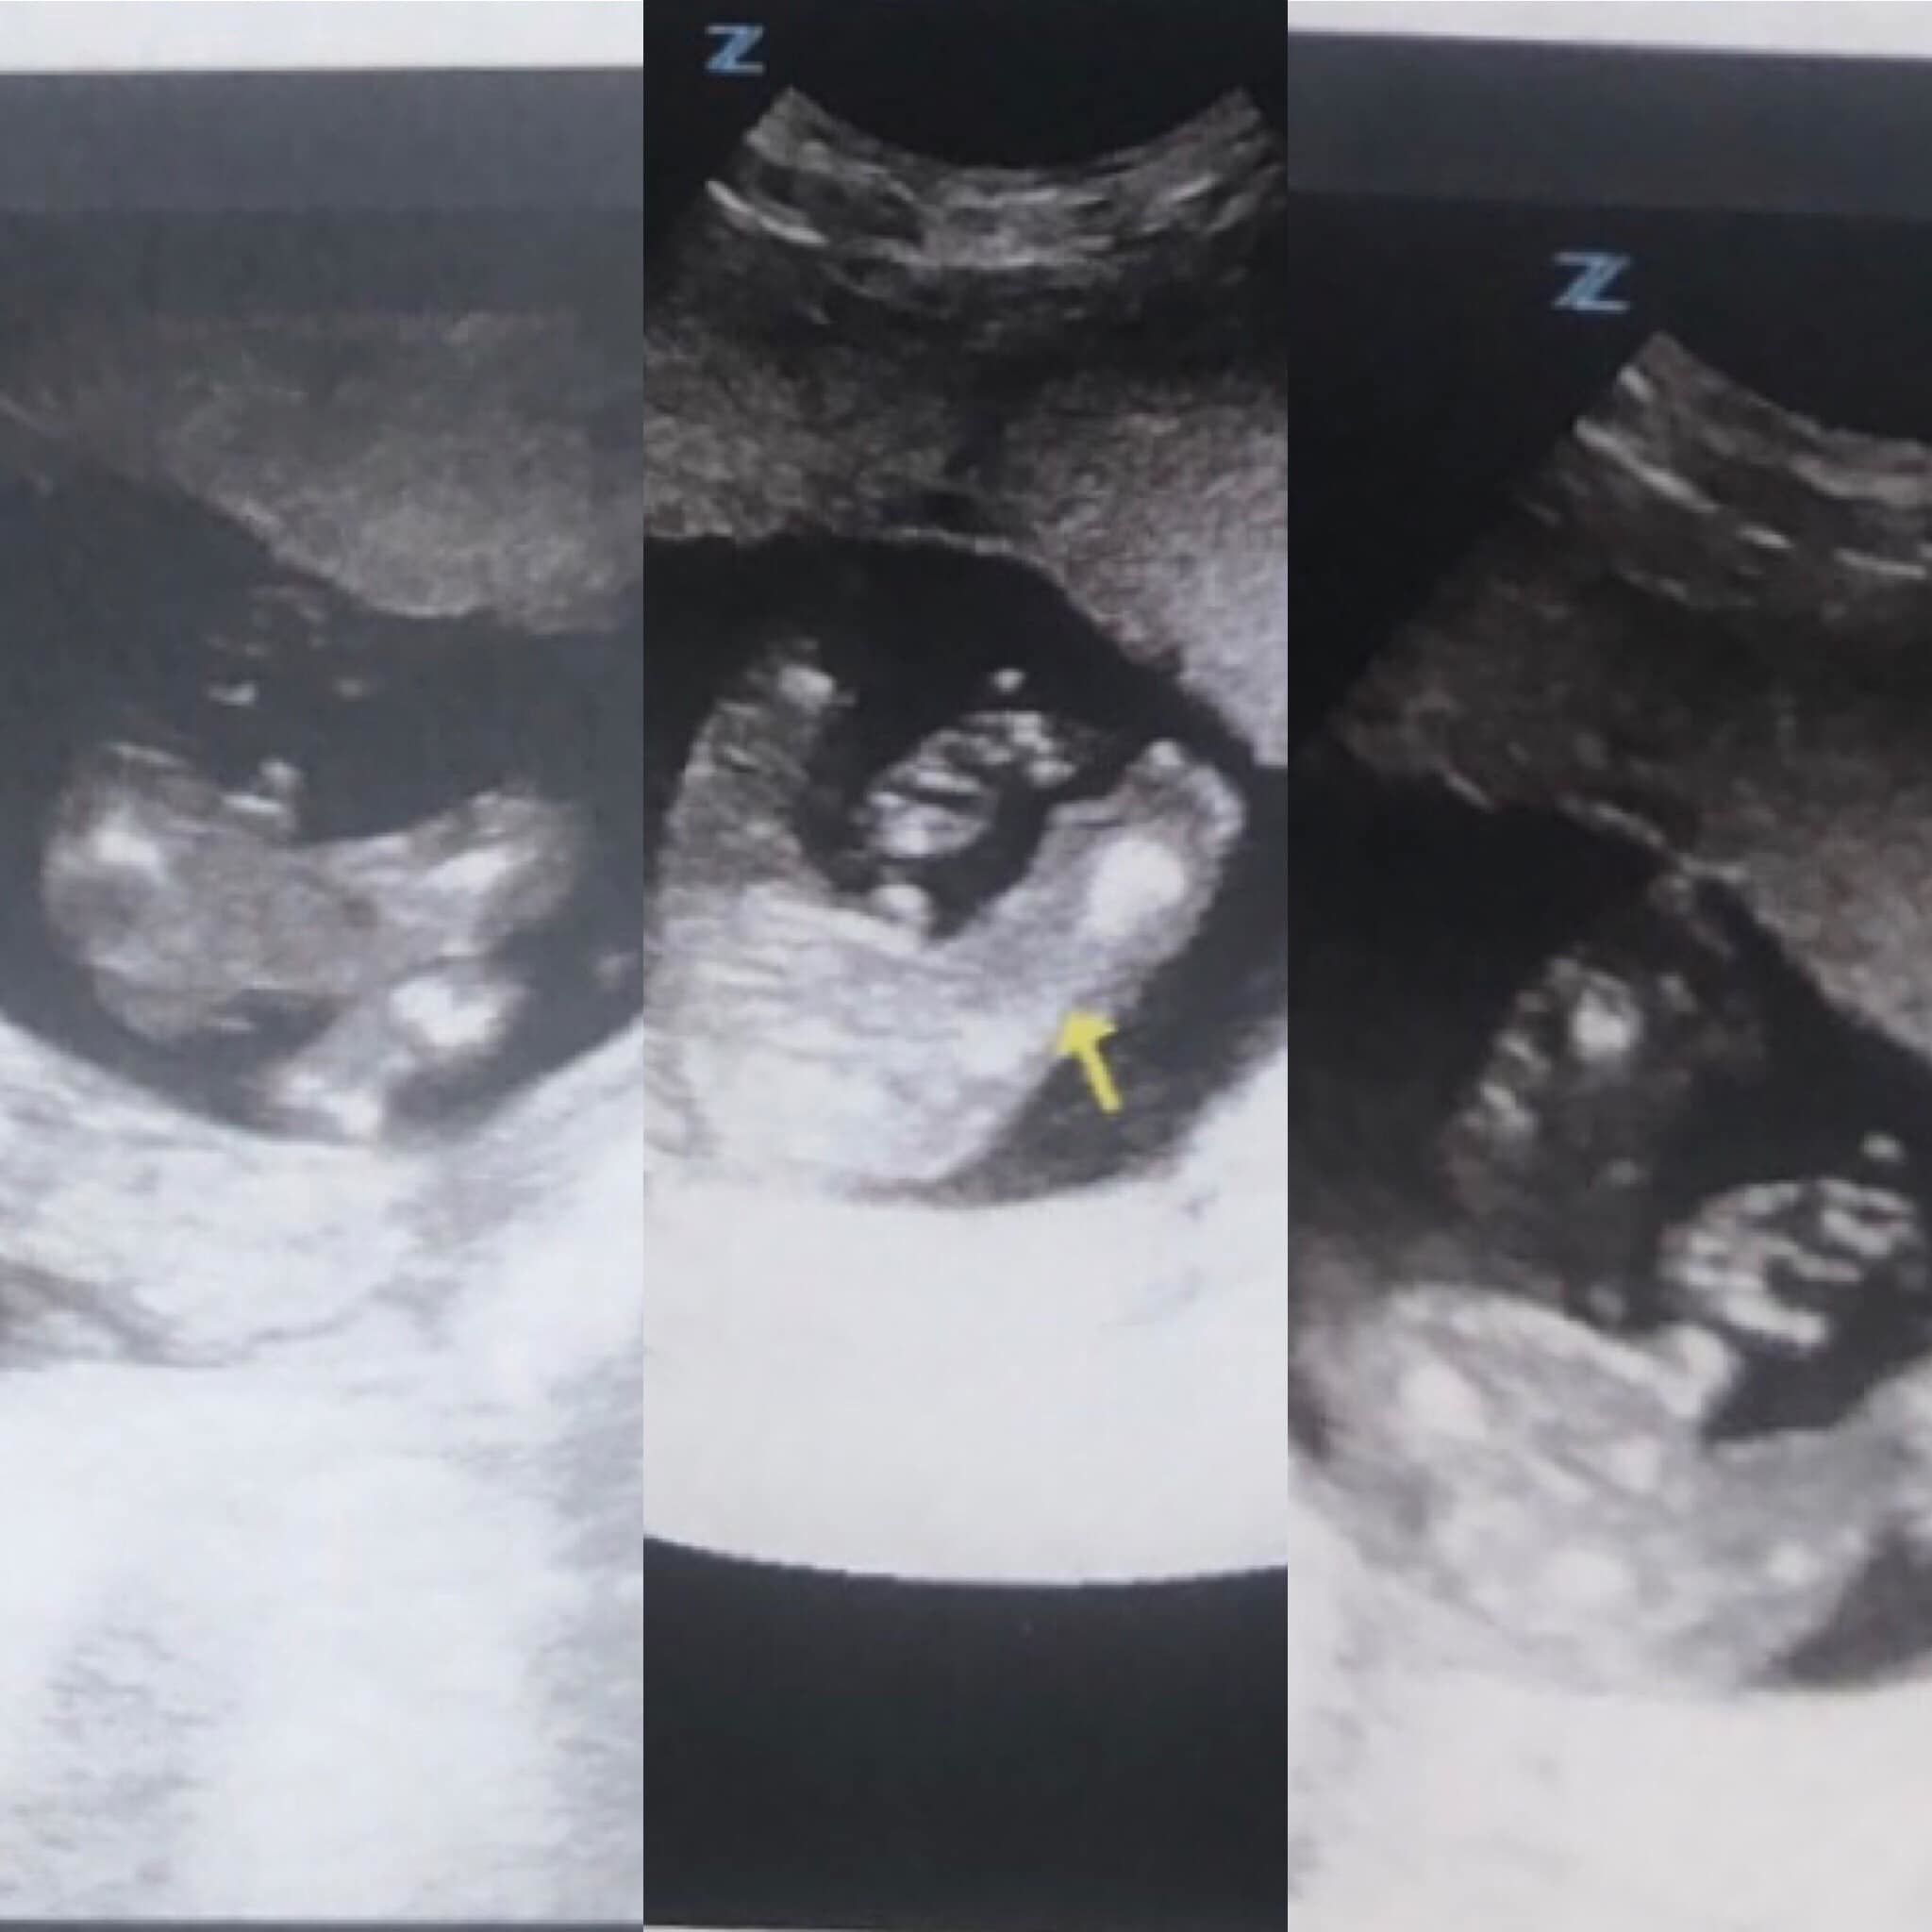

Echographies De Grossesse L Evolution Du Fœtus Semaine Par Semaine

Avis Echo 16sa 2 Gros Doutes Echographie Connaitre Le Sexe De Votre Bebe Forum Grossesse Amp Bebe Doctissimo

Echographie 16sa 1 Youtube

3 Eme Rendez Vous Gygy 3 Eme Echo 16 Sa 5 Jours Soit 3 Mois Et Demi De Grossesse My Sweet Dream